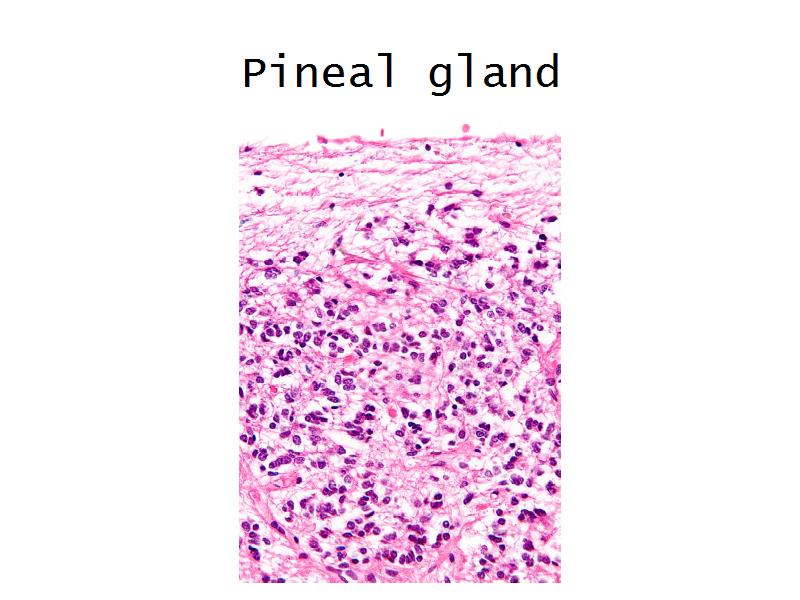

- Pineal gland

- C1: Pineal gland

- C1: Pineal gland = melatonin

- G4: Pineal gland

- G4: Pineal gland = in the midline of the brain behind the third ventricle

- Slide 34: Pineal gland

Pineal Gland